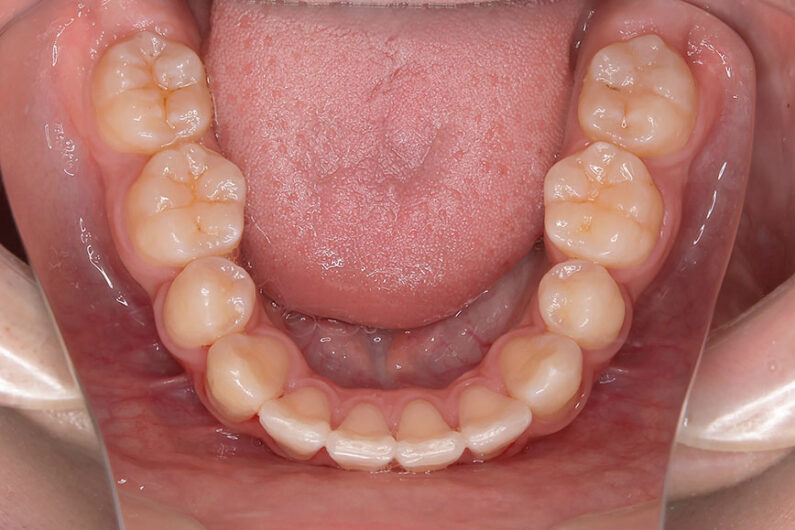

歯が重なっている、出っ歯を治したい 以前に治療した方からの紹介で来院した患者さんです。 上下顎前歯部の叢生(がたつき)、上下顎前歯の前方傾斜、 骨格的上顎前突傾向でした。 小児矯正で叢生の緩和を行い、 本格矯正で前方傾斜した前歯の改善を行いました。 マルチブラケット 動的治療期間 3年3か月 調整回数25回